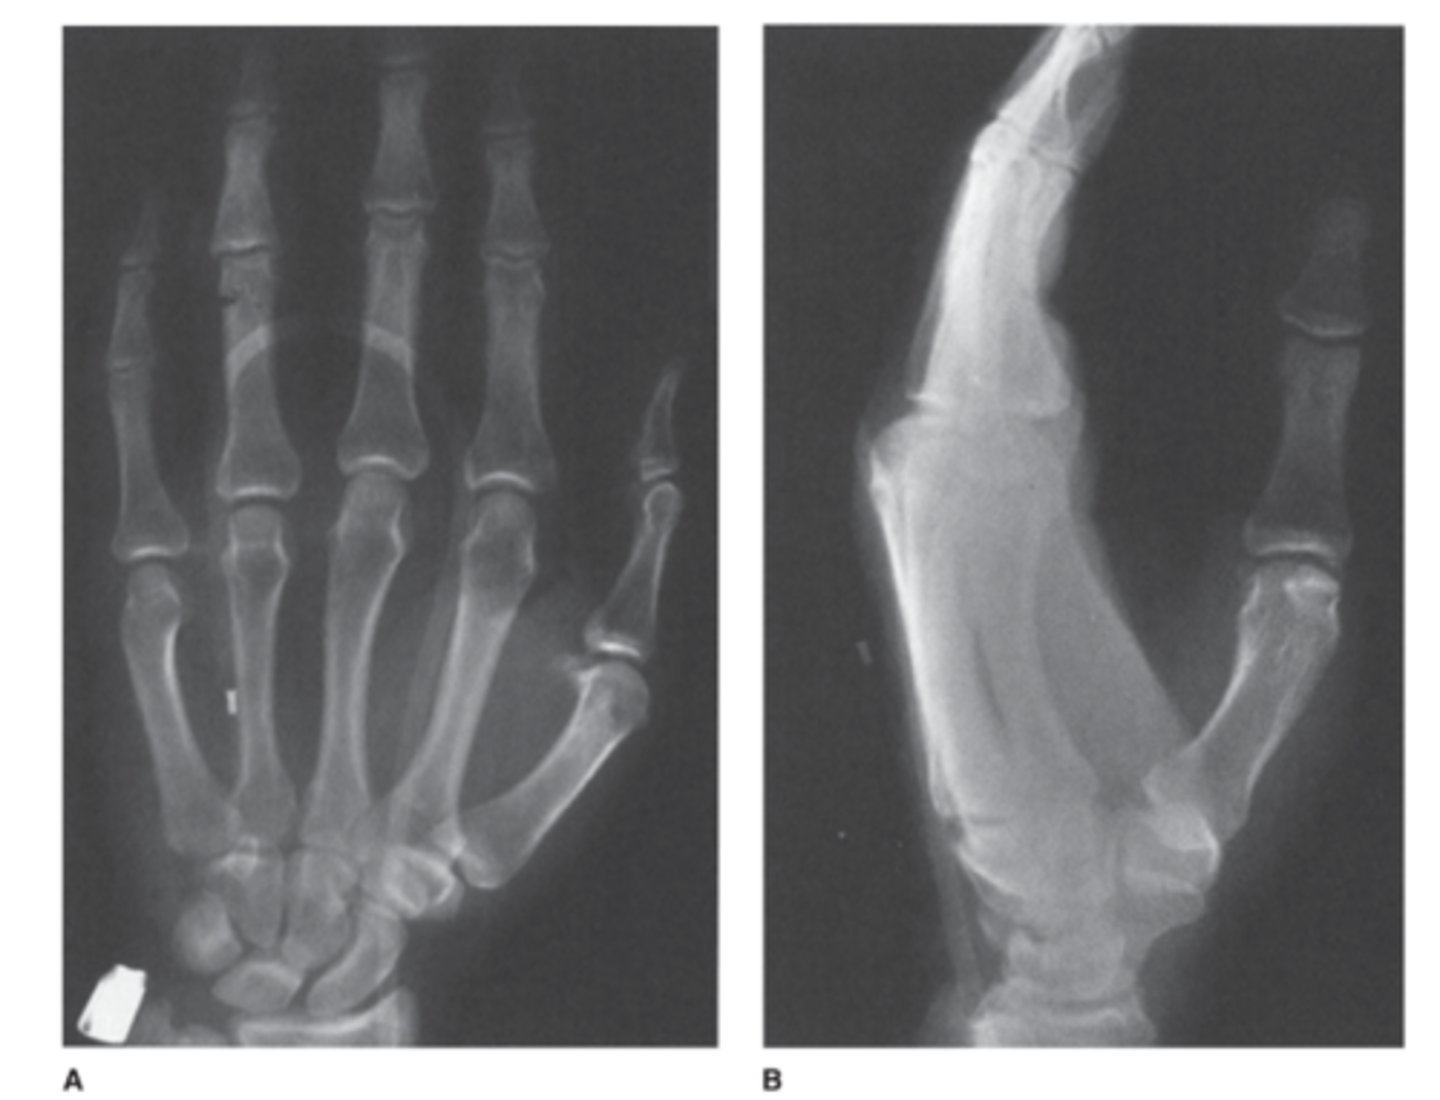

What is fractured here?

answer

View: AP and lateral radiographs

You cant see anything on the lateral, but on the AP you can see a phalangeal fracture of the 4th phalanx.

Wheres the fracture in this one? 1st scan is 2.5 months earlier

intra-articular fracture of the proximal aspect of the middle phalanx